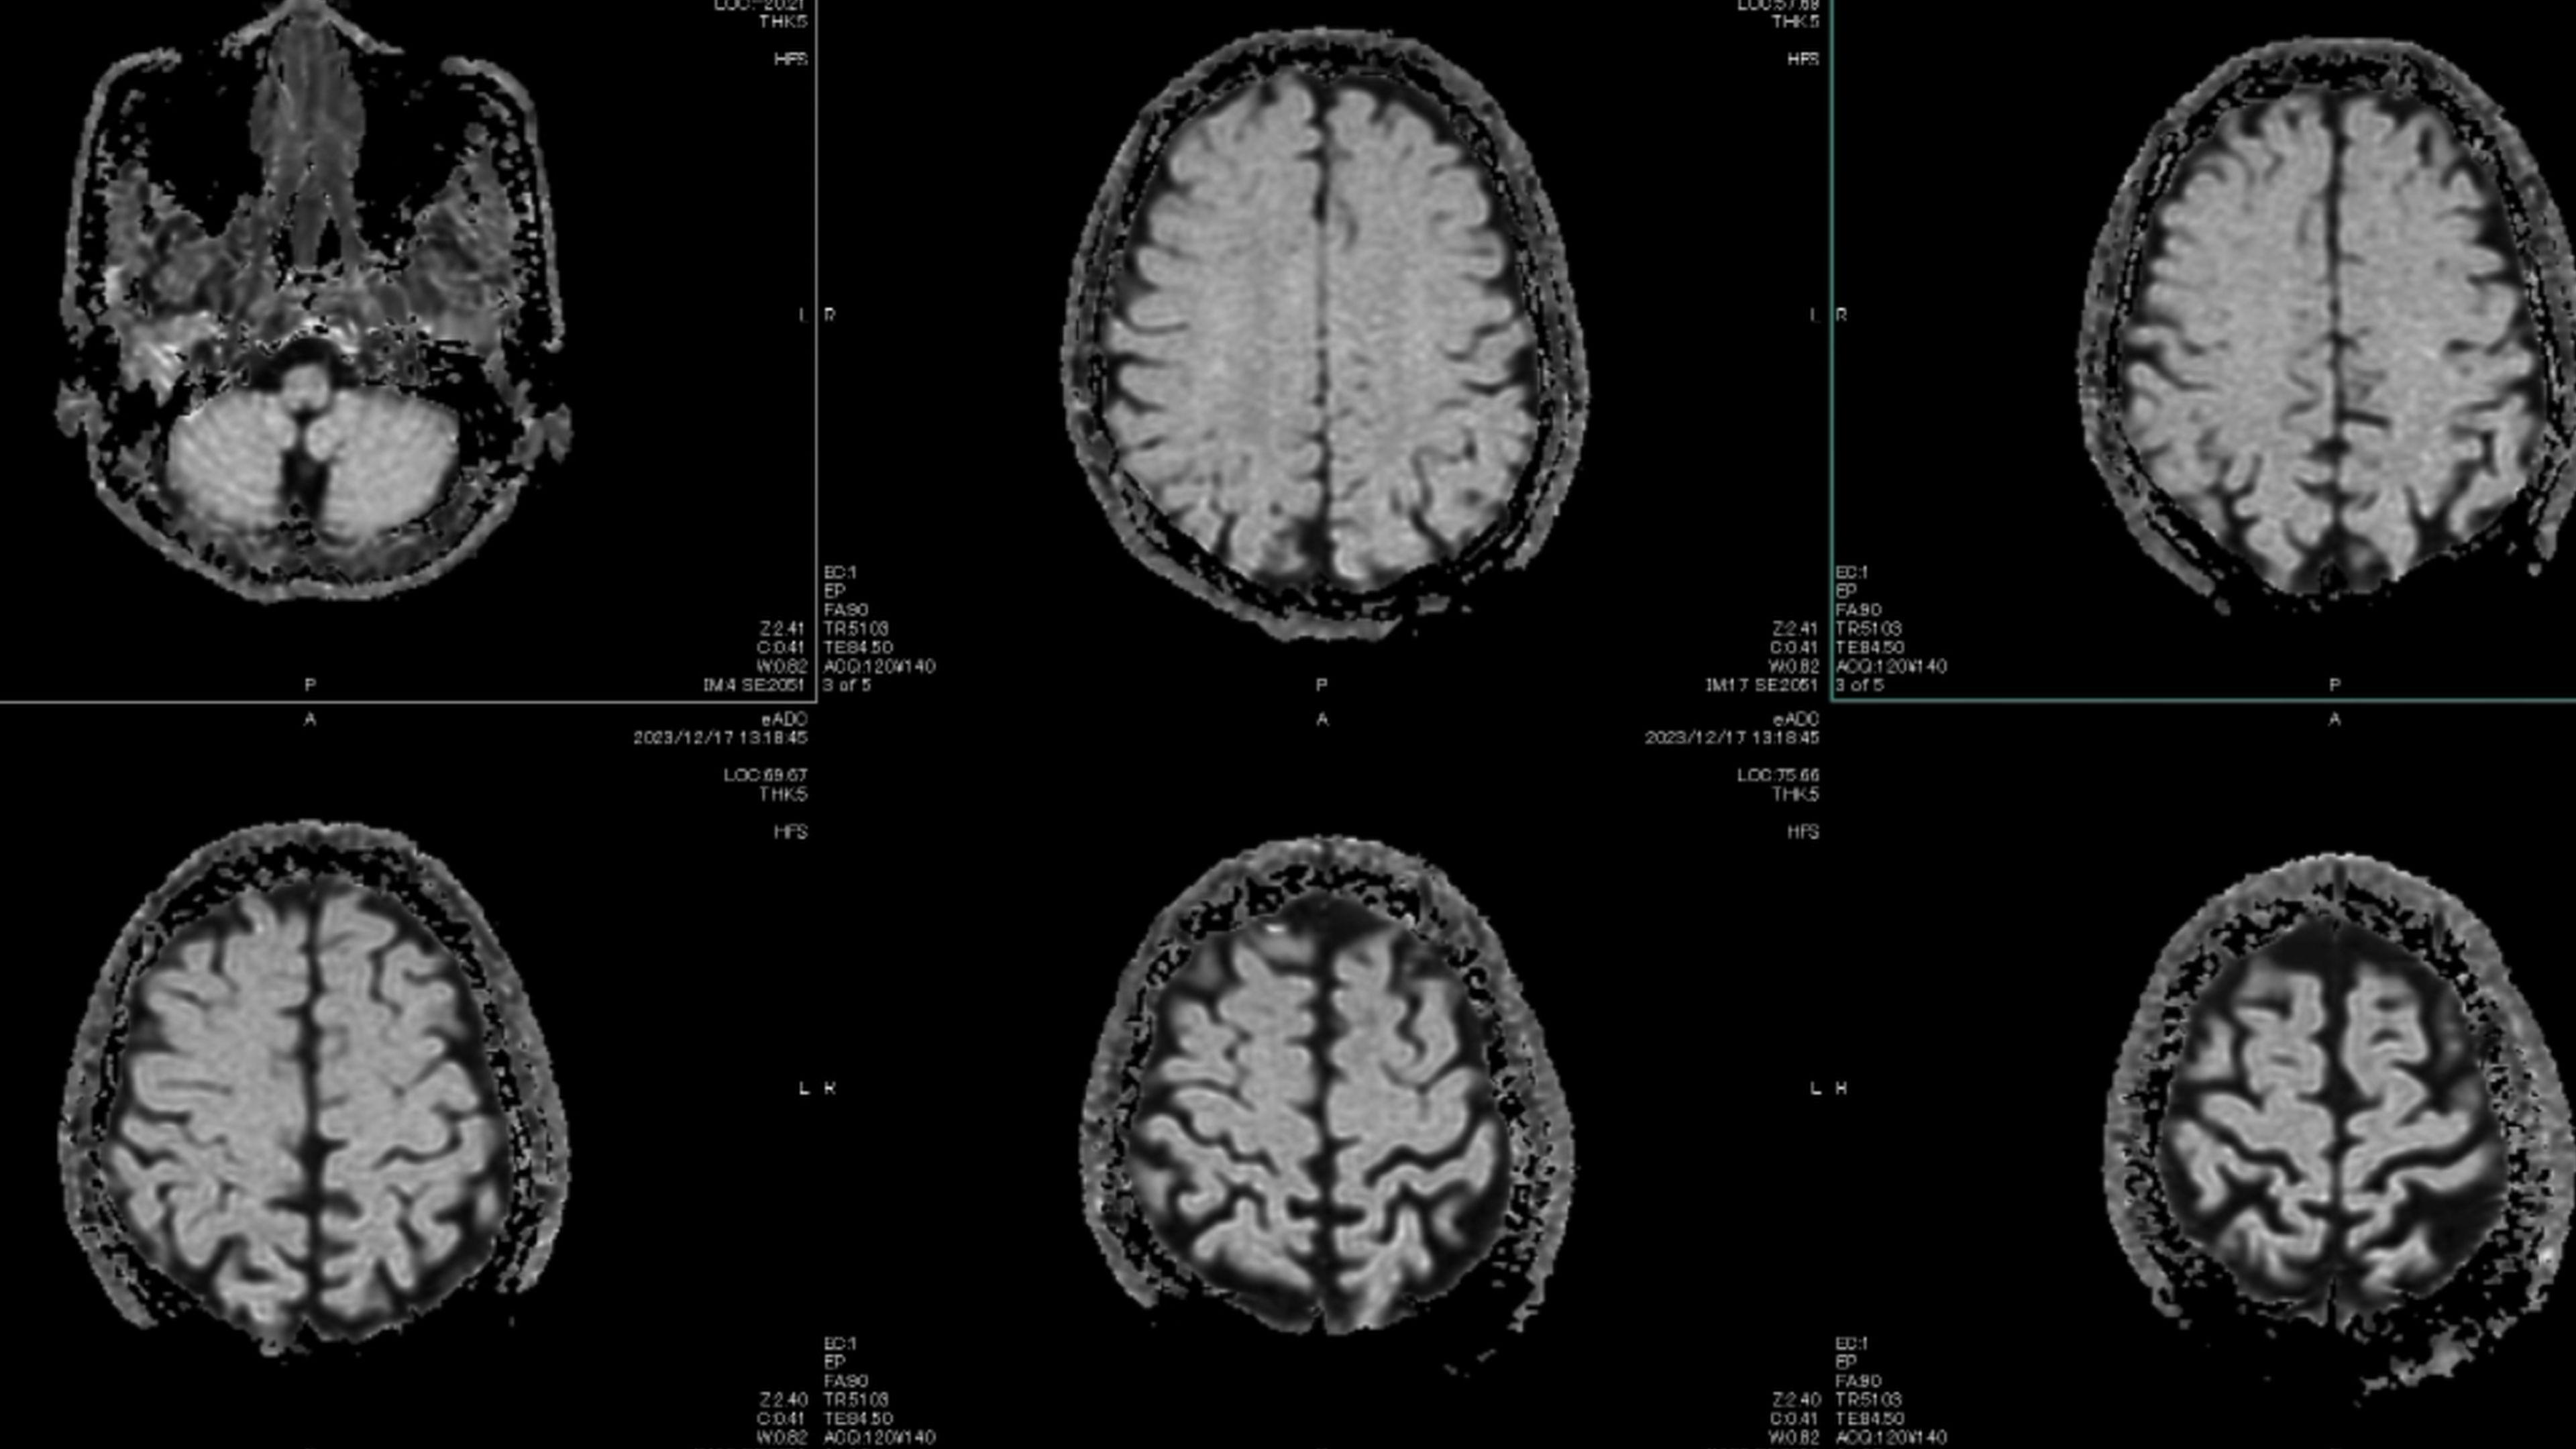

A principal teoria entre os cientistas que estudam o papel do cérebro na enxaqueca é que o ataque é uma onda elétrica lenta e anormal, que se espalha através do córtex cerebral, conhecida como depressão cortical alastrante (CSD, na sigla em inglês).

Esta onda suprime a atividade cerebral e faz disparar os nervos próximos que causam a dor, fazendo soar o alarme e gerando inflamações.

Em março de 2025, cientistas capturaram a onda em tempo real, enquanto monitoravam o cérebro de uma paciente de 32 anos, sendo preparada para cirurgia. Eles captaram a onda através de 95 eletrodos inseridos no seu crânio.

Ela se espalhou a partir do seu córtex visual, o que explica por que algumas pessoas apresentam sensibilidade à luz e visões de auras, segundo Moskowitz. Dali, ela atravessou todo o cérebro por mais 80 minutos.

A variação da natureza da onda ajuda a explicar por que algumas pessoas veem apenas uma aura, outras veem uma aura antes da dor de cabeça e há um grupo que tem dor de cabeça antes da aura, segundo Moskowitz. Tudo depende dos padrões da onda.

Mas a depressão cortical alastrante também explica outros sintomas neurológicos que surgem durante um ataque de enxaqueca, como a fadiga, bocejos, nevoeiro cerebral e vontade de comer alimentos específicos.

O fundamental é que nem o córtex visual, nem o hipotálamo, são o local da dor da enxaqueca.

A dor de cabeça ocorre nas fibras nervosas das meninges, aquela membrana externa do cérebro, espessa e gelatinosa, com três camadas. E também através de um feixe nervoso espesso chamado gânglio trigeminal, que conecta as meninges a estímulos do rosto, do couro cabeludo e dos olhos.